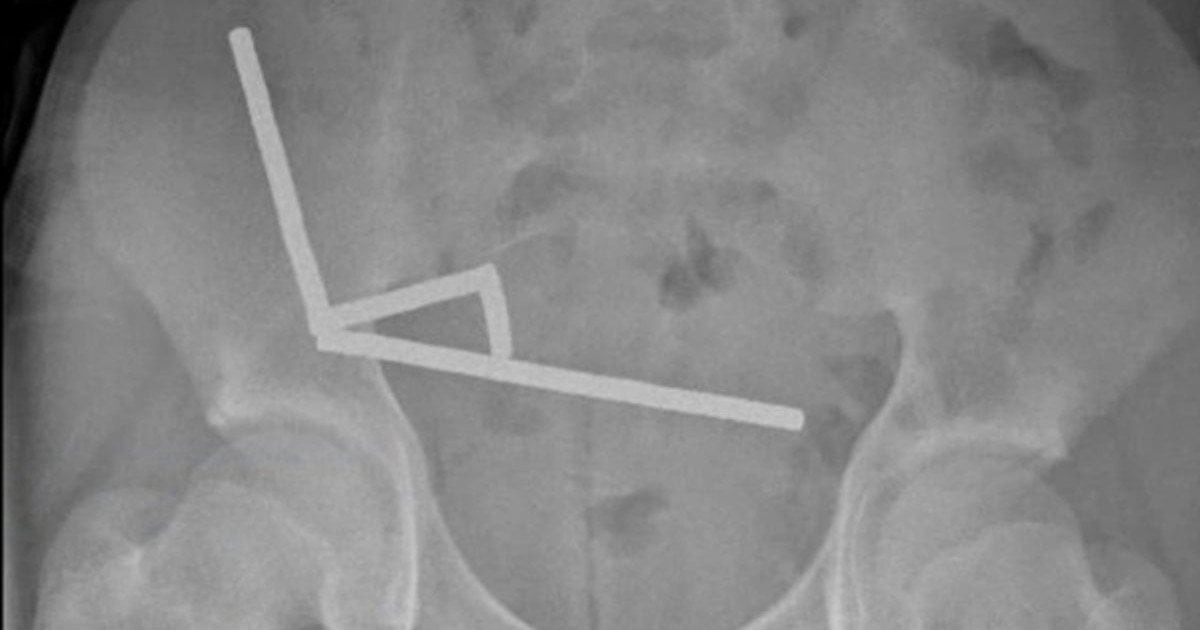

Хлопчик зізнався лікарям, що тиждень тому проковтнув, як він припускав, близько 100 магнітів. Рентгенівський знімок показав, що в його кишечнику утворилися чотири лінійні ланцюги. Ці магніти, з’єднавшись через стінки кишківника, стискали тканини, спричиняючи некроз під тиском (відмирання тканин через брак крові). Незважаючи на складну операцію, підліток одужав і його виписали через вісім днів.